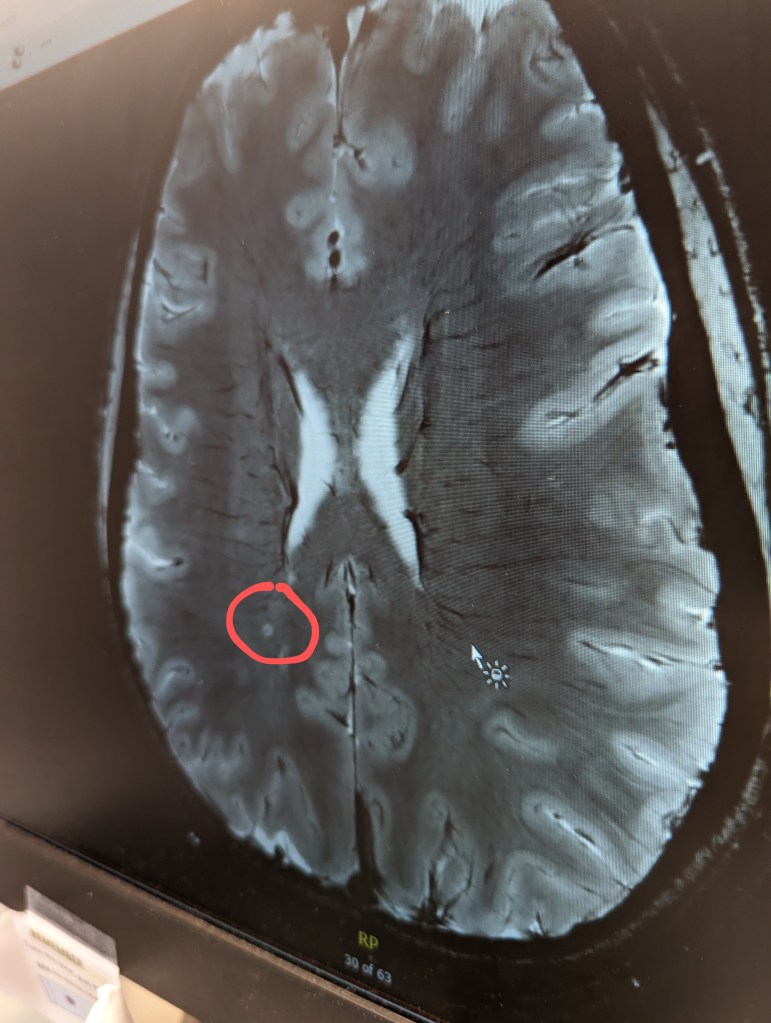

Images above are my brain. The red circle represents one of my very few brain lesions. The image on the left maps water movement throughout my brain.